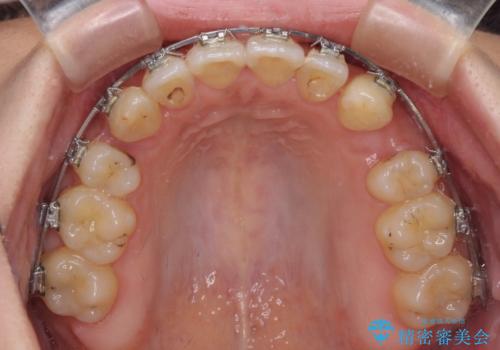

八重歯を抜歯矯正でスッキリと メタルブラケットでの矯正治療

- 矯正装置

- メタルブラケット

- 八重歯と上下前歯のでこぼこを気にして来院された患者様です。

上下前歯部叢生のスペース獲得のため、上下顎左右小臼歯各1歯(計4本)と全ての親知らずを抜歯して、矯正治療を行うこととしました。